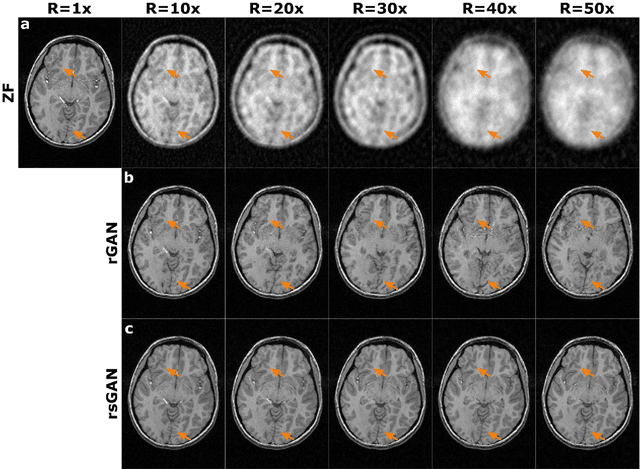

Multi-contrast MRI acquisitions of an anatomy enrich the magnitude of information available for diagnosis. Yet, excessive scan times associated with additional contrasts may be a limiting factor. Two mainstream approaches for enhanced scan efficiency are reconstruction of undersampled acquisitions and synthesis of missing acquisitions. In reconstruction, performance decreases towards higher acceleration factors with diminished sampling density particularly at high-spatial-frequencies. In synthesis, the absence of data samples from the target contrast can lead to artefactual sensitivity or insensitivity to image features. Here we propose a new approach for synergistic reconstruction-synthesis of multi-contrast MRI based on conditional generative adversarial networks. The proposed method preserves high-frequency details of the target contrast by relying on the shared high-frequency information available from the source contrast, and prevents feature leakage or loss by relying on the undersampled acquisitions of the target contrast. Demonstrations on brain MRI datasets from healthy subjects and patients indicate the superior performance of the proposed method compared to previous state-of-the-art. The proposed method can help improve the quality and scan efficiency of multi-contrast MRI exams.